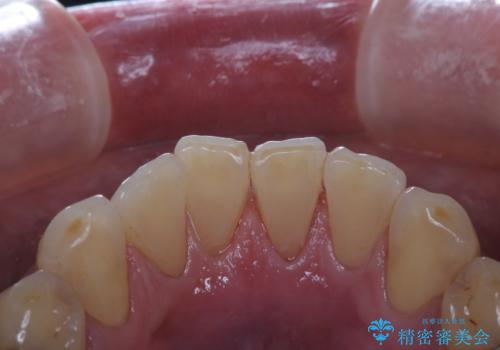

プラークが放置されると、そこで歯周病菌が繁殖し始めます。よって歯肉に炎症が生じ、歯周病に引き金となります。

クリーニングを行うことで、汚れがを取り除くだけではなく、口臭予防にもなります。

またPMTCを行うことで、ご自身本来の歯の色になり自然な明るさになります。